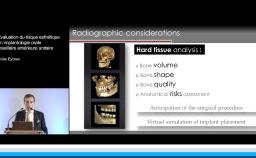

Le point central est l’objectif prothétique puisque la position tridimensionnelle de l’implant placé lors de la phase chirurgicale est dictée par le résultat prothétique souhaité. Ainsi, l’orateur revient sur les critères fondamentaux à respecter pour positionner idéalement l’implant par rapport aux dents adjacentes et à la crête osseuse résiduelle. Ensuite, des méthodes de correction osseuse, gingivale et prothétique visant à améliorer le résultat final sont présentées. La classification retenue est basée sur la sévérité de la perte de volume des tissus osseux et gingivaux adjacents à l’édentement, avec pour objectif d’obtenir un résultat prothétique harmonieux.

- d’anticiper la difficulté de réhabilitation implantaire dans la zone esthétique

- de définir un protocole chirurgical en fonction des objectifs prothétiques

- de connaître les critères de placement tridimensionnel de l’implant dans le secteur antérieur